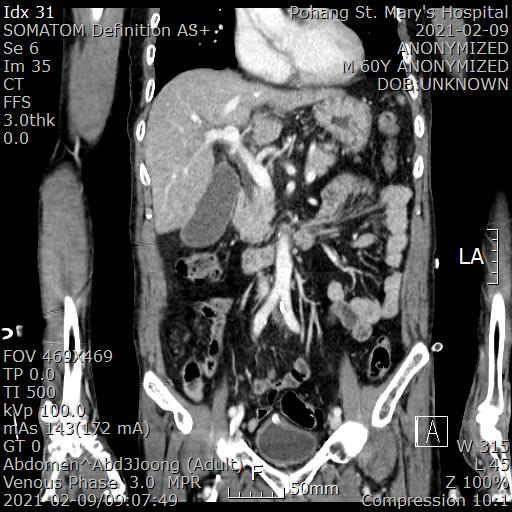

[복부 CT 판독]

1. GB distension & wall thickening

---> R/O Early finding of acute cholecystitis

2. Hepatic surface irrgularity with fatty infiltration

---> Liver cirrhosis, suggested

- no evidence of HCC

- no splenomegaly

- no ascites

여전히 담낭염 소견이 의심되는 상황이고 진전섬망 및 대사상 산증이 많이 회복되어 수술로써 담낭을 절제하는 것이 낫다는 판단을 했습니다.